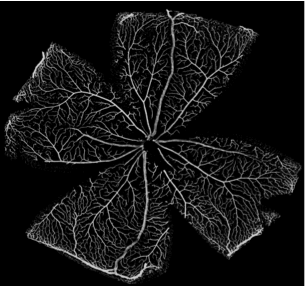

One of the pressing questions in the field is establishing how primitive vessel networks remodel into a hierarchically branched and functionally perfused network of arteries, arterioles, capillaries, and venules (Figure 1). In recent years, the main molecular mechanisms regulating endothelial cell behaviour during vessel formation have been elucidated using experimental techniques (Jones et al.,, 2006; Potente et al.,, 2011). However, important challenges remain: i) understanding how cell-level mechanisms integrate to give rise to systems-level behaviour and, ii) understanding the impact in vascular patterning of the interplay between cellular molecular regulation and haemodynamic forces (i.e. vascular mechanotransduction). These problems are hard to address due to the multiscale and multiphysics nature of the processes involved. Systems-level behaviour arises from highly non-linear, tightly coupled interactions between subprocesses at different spatial and temporal scales. Furthermore, it has been recently proposed (Bentley et al.,, 2013) that a tighter integration between experimental and computational work is required in order to tackle these questions. Working in a feedback loop, computational models should be capable of generating new hypotheses, rather than merely reproducing experimental data. In turn, experiments should provide new biological insights based on these hypotheses and help to further refine computational models.

The vascular plexus of wildtype retinas was stained with the luminal membrane marker ICAM2 and images were acquired using a confocal microscope as described in Section 33.1. Figure 5 shows a region of interest in one of the imaged retinas. It contains, on either side, two arterial segments coming from the optic disc and connecting with a segment of a retinal vein (centre of the image) through a dense capillary network. It can be appreciated how the network is more mature (e.g. vessel identity, branching patterns) closer to the optic disc (bottom of the image) while its structure is much more primitive and less remodelled in the periphery closer to the sprouting front (top of the image). Figure 5 presents the results of the image segmentation process. The algorithm described in Section 33.1 is used to first create a binary mask separating the luminal area and background tissue and second extract the network skeleton and radii. The latter are used to reconstruct the 3D luminal surface under the assumption of vessel circular cross-section (see Section 33.1 for a discussion). Figure 5 shows the reconstructed surface. We refer to this model as P6A.

Figure 6 presents luminal surface binary masks for three additional P5 and P6 retinal plexuses. The same reconstruction algorithm is applied and the resulting models are referred to as P5A, P5B, and P6B, respectively.